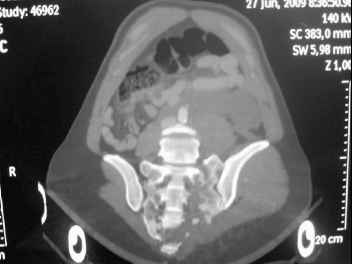

41 yo female , fall from 10 meters five days ago. Hemodynamically unstable on admission treated by angio and embolization and skeletal traction, with no external support. No associated injuries.

Based on CT scan the pt has a both column fracture with conminuted dome and displaced anterior column and a sacral Denis 1 fracture with a displaced left ala. I think the best approach for the acetabular fracture is ilioinguinal with Smith-Petersen extension but don't know exactly the sequence . Will you start with the sacral fracture? Which technique?